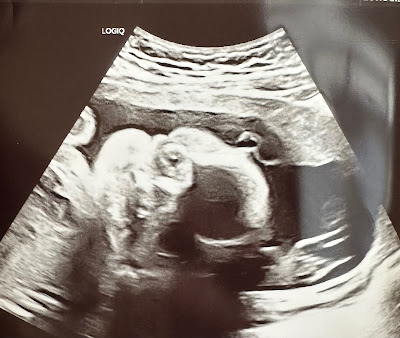

As I waited for our second anatomy scan I found myself comparing Georgi’s and Stetson’s ultrasound pictures to this baby’s. Of course I don’t have the skills to understand what I’m truly looking at but I could certainly tell a massive difference in the profile. Georgi and Stetson both had such cute little button noses completely visible on the scan. Baby boy on the other hand looked as if he had no nose at all. I felt like his face was practically smooth with very minimal divots and ridges to bring out any prominent features. I truly wish I could stay positive but to be honest I felt like no matter how much I asked and prayed for a good outcome I wasn’t going to get it.

This time baby cooperated so we could see his head better. We could see clearly the misshapenness, clear divots dimpled baby’s temple on either side of his head. It was discouraging to see and Levi’s demeanor changed a little somber after we could recognize these abnormalities without the tech or a doctor pointing them out.

When the office called us back I laid on the table and felt my heart racing. I felt uncomfortable and found myself wanting to call out. The first part of the procedure is an incredibly scrupulous ultrasound that took approximately an hour. During the ultrasound Levi and I could visibly notice the swelling around baby. As I watched the screen we could more clearly see baby boy’s misshapen head, his teeny tiny nose, and obvious swelling in the belly and scrotum. I couldn’t help but feel uneasy about the procedure that would take place once the doctor would come in and if I was making a mistake. Even without confirmation from the doctor it was clear that baby boy was exhibiting very similar signs as Stetson.